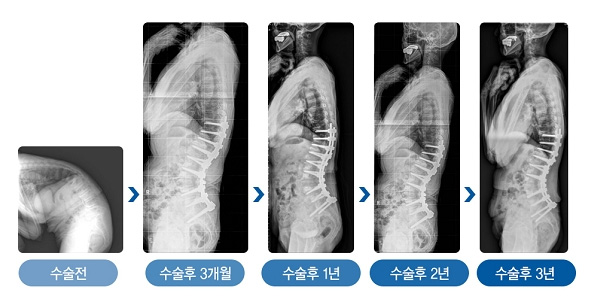

심한 노인성 후만변형으로 수술 받은 78세 환자의 수술 후 3년간 변화 사진/강동경희대병원 제공

김용찬 교수팀은 전방 추체 사이 유합술과 후방기기 고정술을 병합한 새로운 수술방법을 개발했다. 기존 수술 방법에서 추가적으로 추체 사이의 전방 종인대를 함께 부분 절제하는 수술법이다. 기존 추체절골술 후에 완벽한 구현되지 못했던 생리적 허리 곡선을 최대한 구현했으며, 빈번한 불유합으로 인한 재변형에 의한 재수술 발생을 획기적으로 감소시켰다. 또 수술 직후 얻었던 허리 곡선이 오랜 기간 동안 유지됨을 확인했다.